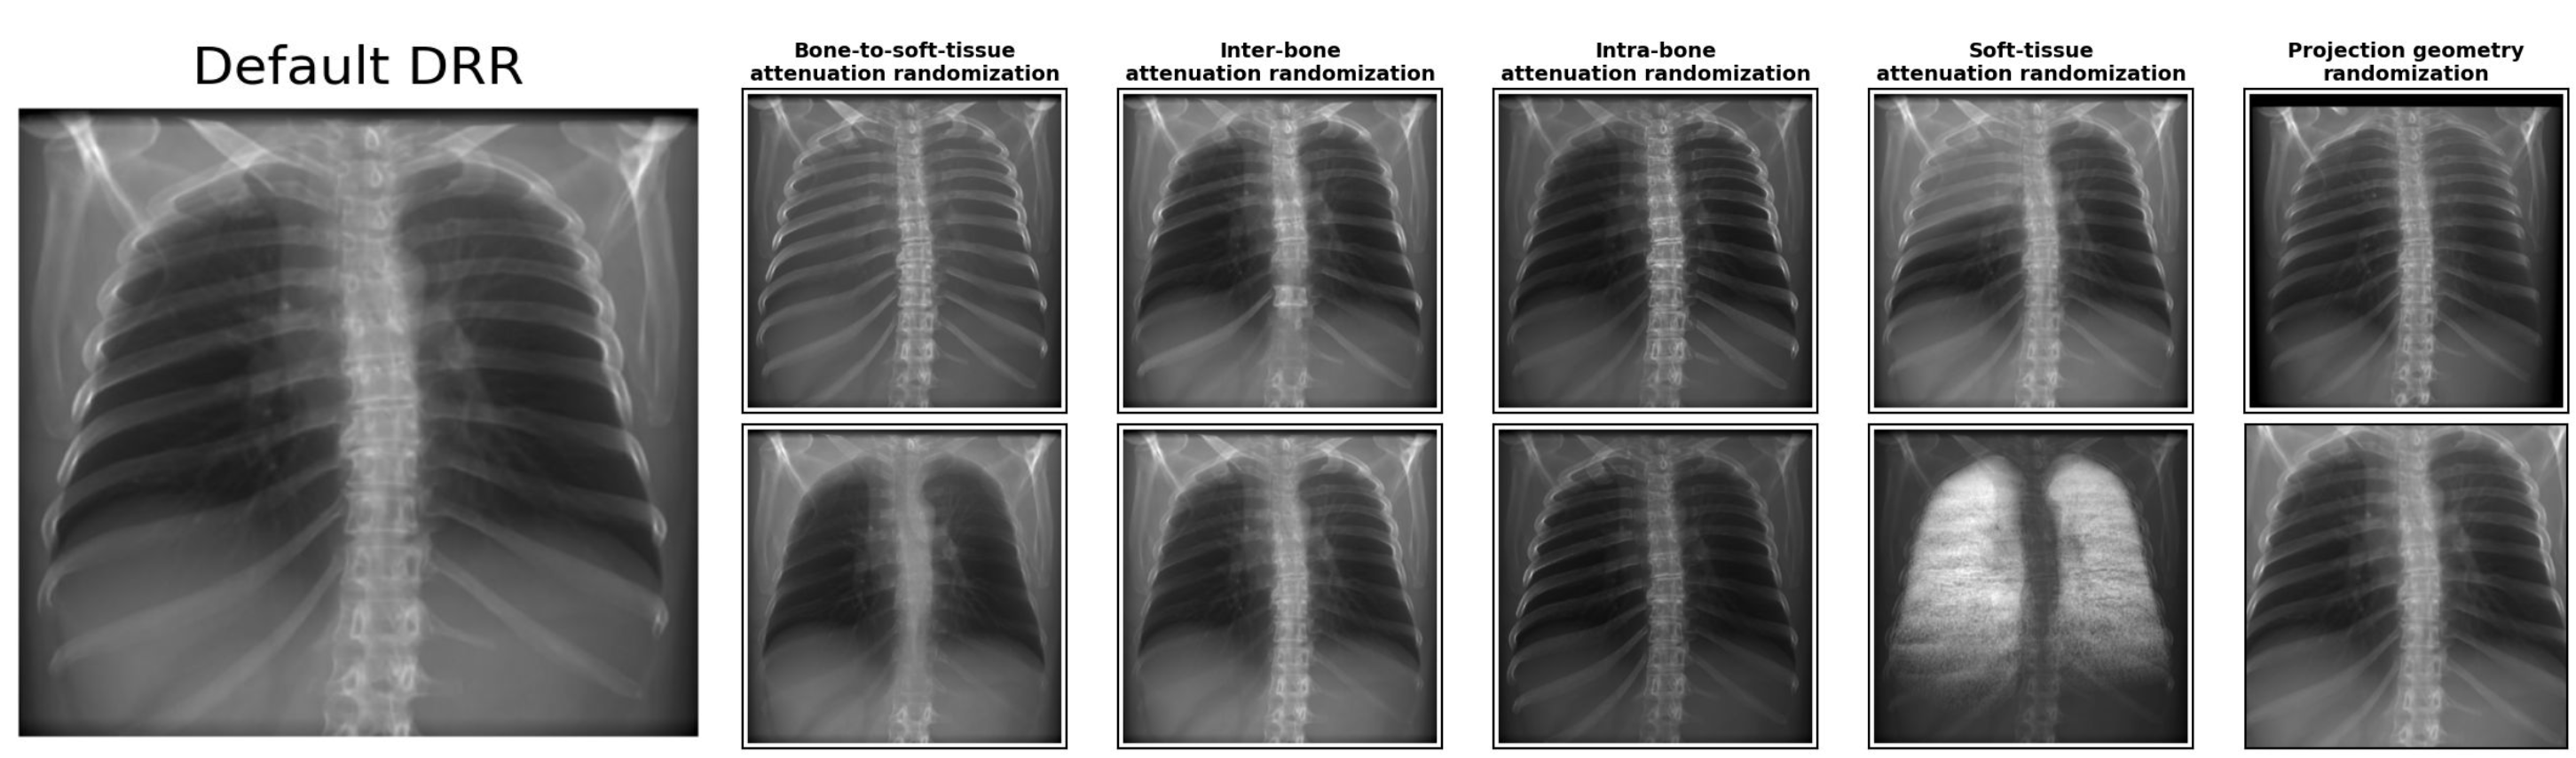

To overcome these limitations, we propose Multi-stage Domain Randomization (MSDR). The workflow is illustrated in Fig. 2 with technical details summarized in A, inspired by Representation Learning [anatomix] and AnyStar [anystar]. Our MSDR engine performs the first stage of randomization directly in 3D before projection. This “pre-projection” strategy perturbs the causes of radiographic variability, producing a richer and more realistic distribution of DRRs. We introduce four principal 3D augmentation modules to modulate Hounsfield Units (HU), simulate structural variability, and alter projection behavior:

•

Bone-to-soft-tissue attenuation randomization: To replicate variations in bone–soft-tissue contrast arising from different exposure settings, we apply anti-correlated scaling factors to bone and soft tissue. Intensities are sampled from complementary intervals to disrupt consistent contrast relationships (e.g., attenuating bone signals while amplifying soft tissue).

Inter-bone attenuation randomization: To enhance bone density heterogeneity, we independently perturb the attenuation of individual osseous components (e.g., vertebrae, ribs) to decouple adjacent structures, or introduce longitudinal intensity gradients to simulate varying anatomical thickness along the superior-inferior axis.

Intra-bone attenuation randomization: To introduce realistic non-uniform bone density, we apply a morphology-based gradient that modulates attenuation as a function of voxel depth. This simulates the natural transition from the dense cortical surface to the trabecular core, creating heterogeneous internal textures.

Soft-tissue attenuation randomization: To prevent the model from over-relying on absolute brightness for segmentation, we apply random multiplicative HU scaling perturbations to soft-tissue regions. Additionally, we introduce polarity inversion to simulate extreme contrast reversals, thereby generating a wider range of appearance variations.

Projection geometry randomization: Source-to-Detector Distance (SDD) and Object-to-Detector Distance (ODD) are determined using available metadata when present. Otherwise, we use dataset-average values from CT-RATE and apply small random drifts to simulate variability in clinical setup.

Together, these pre-projection and post-projection randomizations form the MSDR engine, producing a highly diverse, physically plausible, and label-aligned synthetic CXR dataset for large-scale segmentation training. For a visual overview of the workflow logic and detailed implementation methods, please refer to Fig. 2 and A. We visualize the innovative 3D augmentation effect in Fig. 4.